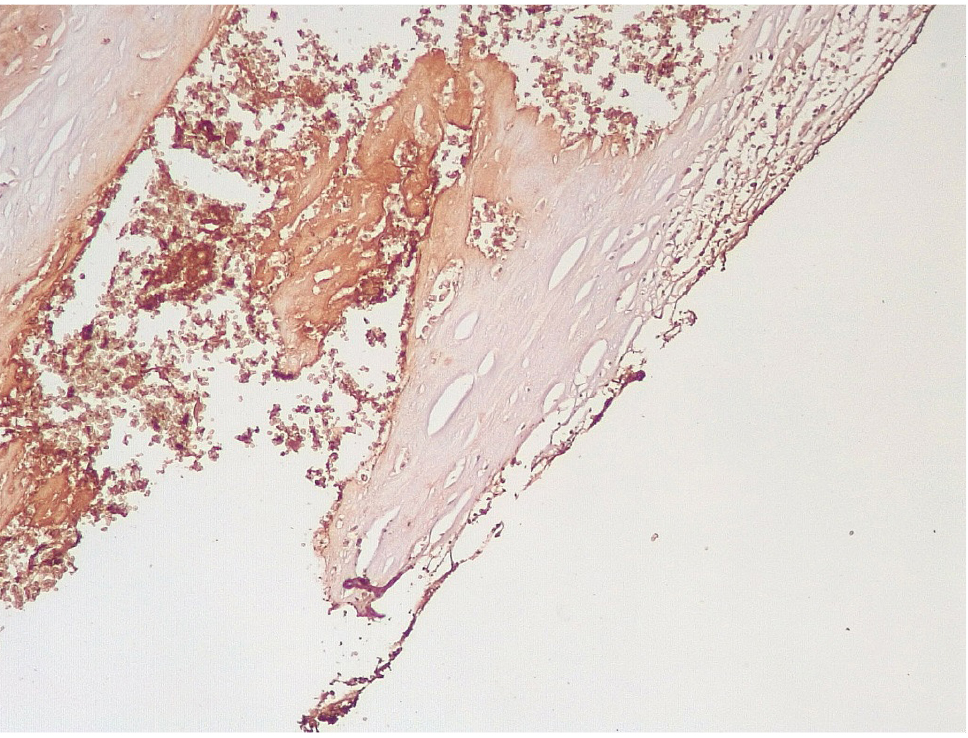

Обращало внимание, что в местах «оголенного» эндотелия КА отмечалась слабая экспрессия белка CD31, что указывало на выраженные дистрофические и некробиотические изменения клеток (рис. 2). При этом экспрессия ФВ была яркой, выраженной на всем протяжении интимы КА (рис. 3).

Сохранялась резковыраженная яркая экспрессия ФВ как со стороны интимы, так и субинтимально, в участках альтерации атером (рис. 8). В то же время экспрессия белка CD31 была негативной на всем протяжении стенок КА.

Наиболее значимым маркером эндотелиальной дисфункции, отражающим нарушение коагуляционных свойств крови, является белок фактор Виллебранда, экспрессия которого была резко выраженной во всех группах умерших после стентирования КА.